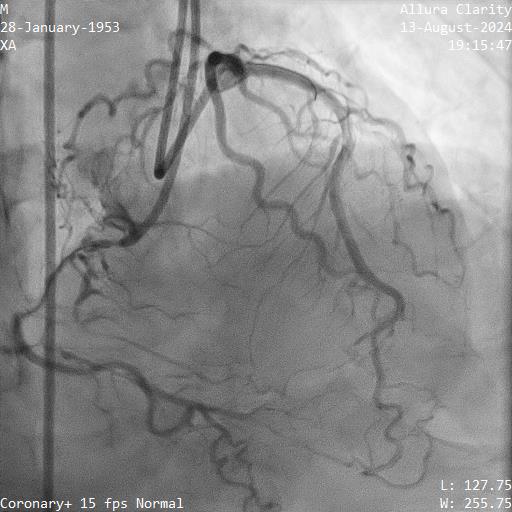

Relevant Catheterization Findings

1. LMT was normal

2. Proximal LAD had a 70-80% stenosis, mid LAD had myocardial bridging. LAD supplied septal collateral (CC) to distal PDA

3. Proximal LCX artery had a 90% stenosis

4. Proximal RCA was diffuse disease 70-80%, mid to distal RCA was a CTO. Ipsilateral CC from marginal to PDA

PCI was performed for LCX with biolimus eluting stent (BES) 2.5x30mm and LAD with BES 3.0x29mm

He was scheduled for stage PCI RCA CTO 2 months later.